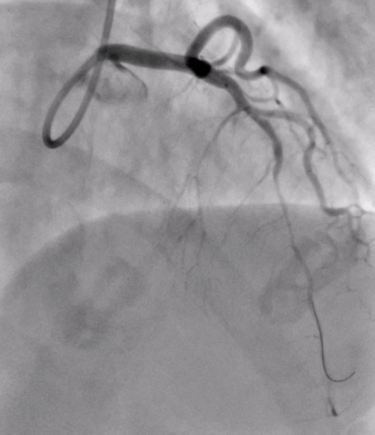

Invasive Angiography with Physiology & VasoReactivity tests

Advanced & Guidelines-Indicated State-of-the Art Invasive Diagnostics